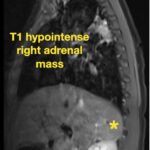

Pediatric neuroblastoma is famously characterized by an abdominal mass in a toddler with “raccoon eyes,” Horner syndrome, and/or opsoclonus myoclonus. However, rare cases may present with non-discrete symptoms and signs which create challenges for timely diagnosis. This case depicts a toddler with bulbar symptoms, including bilateral ptosis, dysphagia, drooling, head tilt and ataxia in a post-viral course mimicking other neurologic diagnoses, including myasthenia gravis. Magnetic resonance imaging (MRI) of the brain and spine uncovered a right adrenal mass along with heterogenous enhancement in multiple vertebral bodies and the clivus, consistent with metastatic disease. A diagnosis of neuroblastoma was confirmed with elevated homovanillic acid (HMA) and vanillylmandelic acid (VMA) levels and adrenal biopsy. The patient was treated with plasmapheresis for suspected paraneoplastic neurological syndrome and subsequent chemotherapy. In this case presentation, we review neurologic syndromes causing acute-onset pediatric bulbar weakness along with the patient’s key MRI findings.